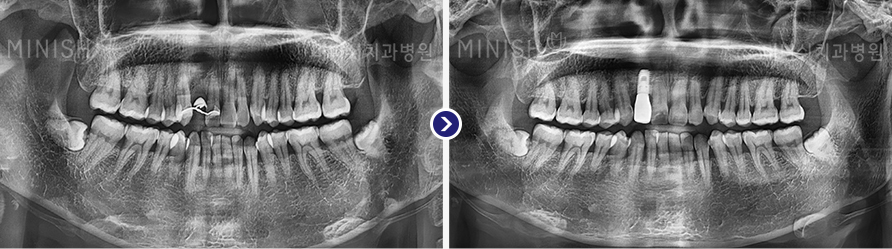

种植牙前后变化

01 X光片